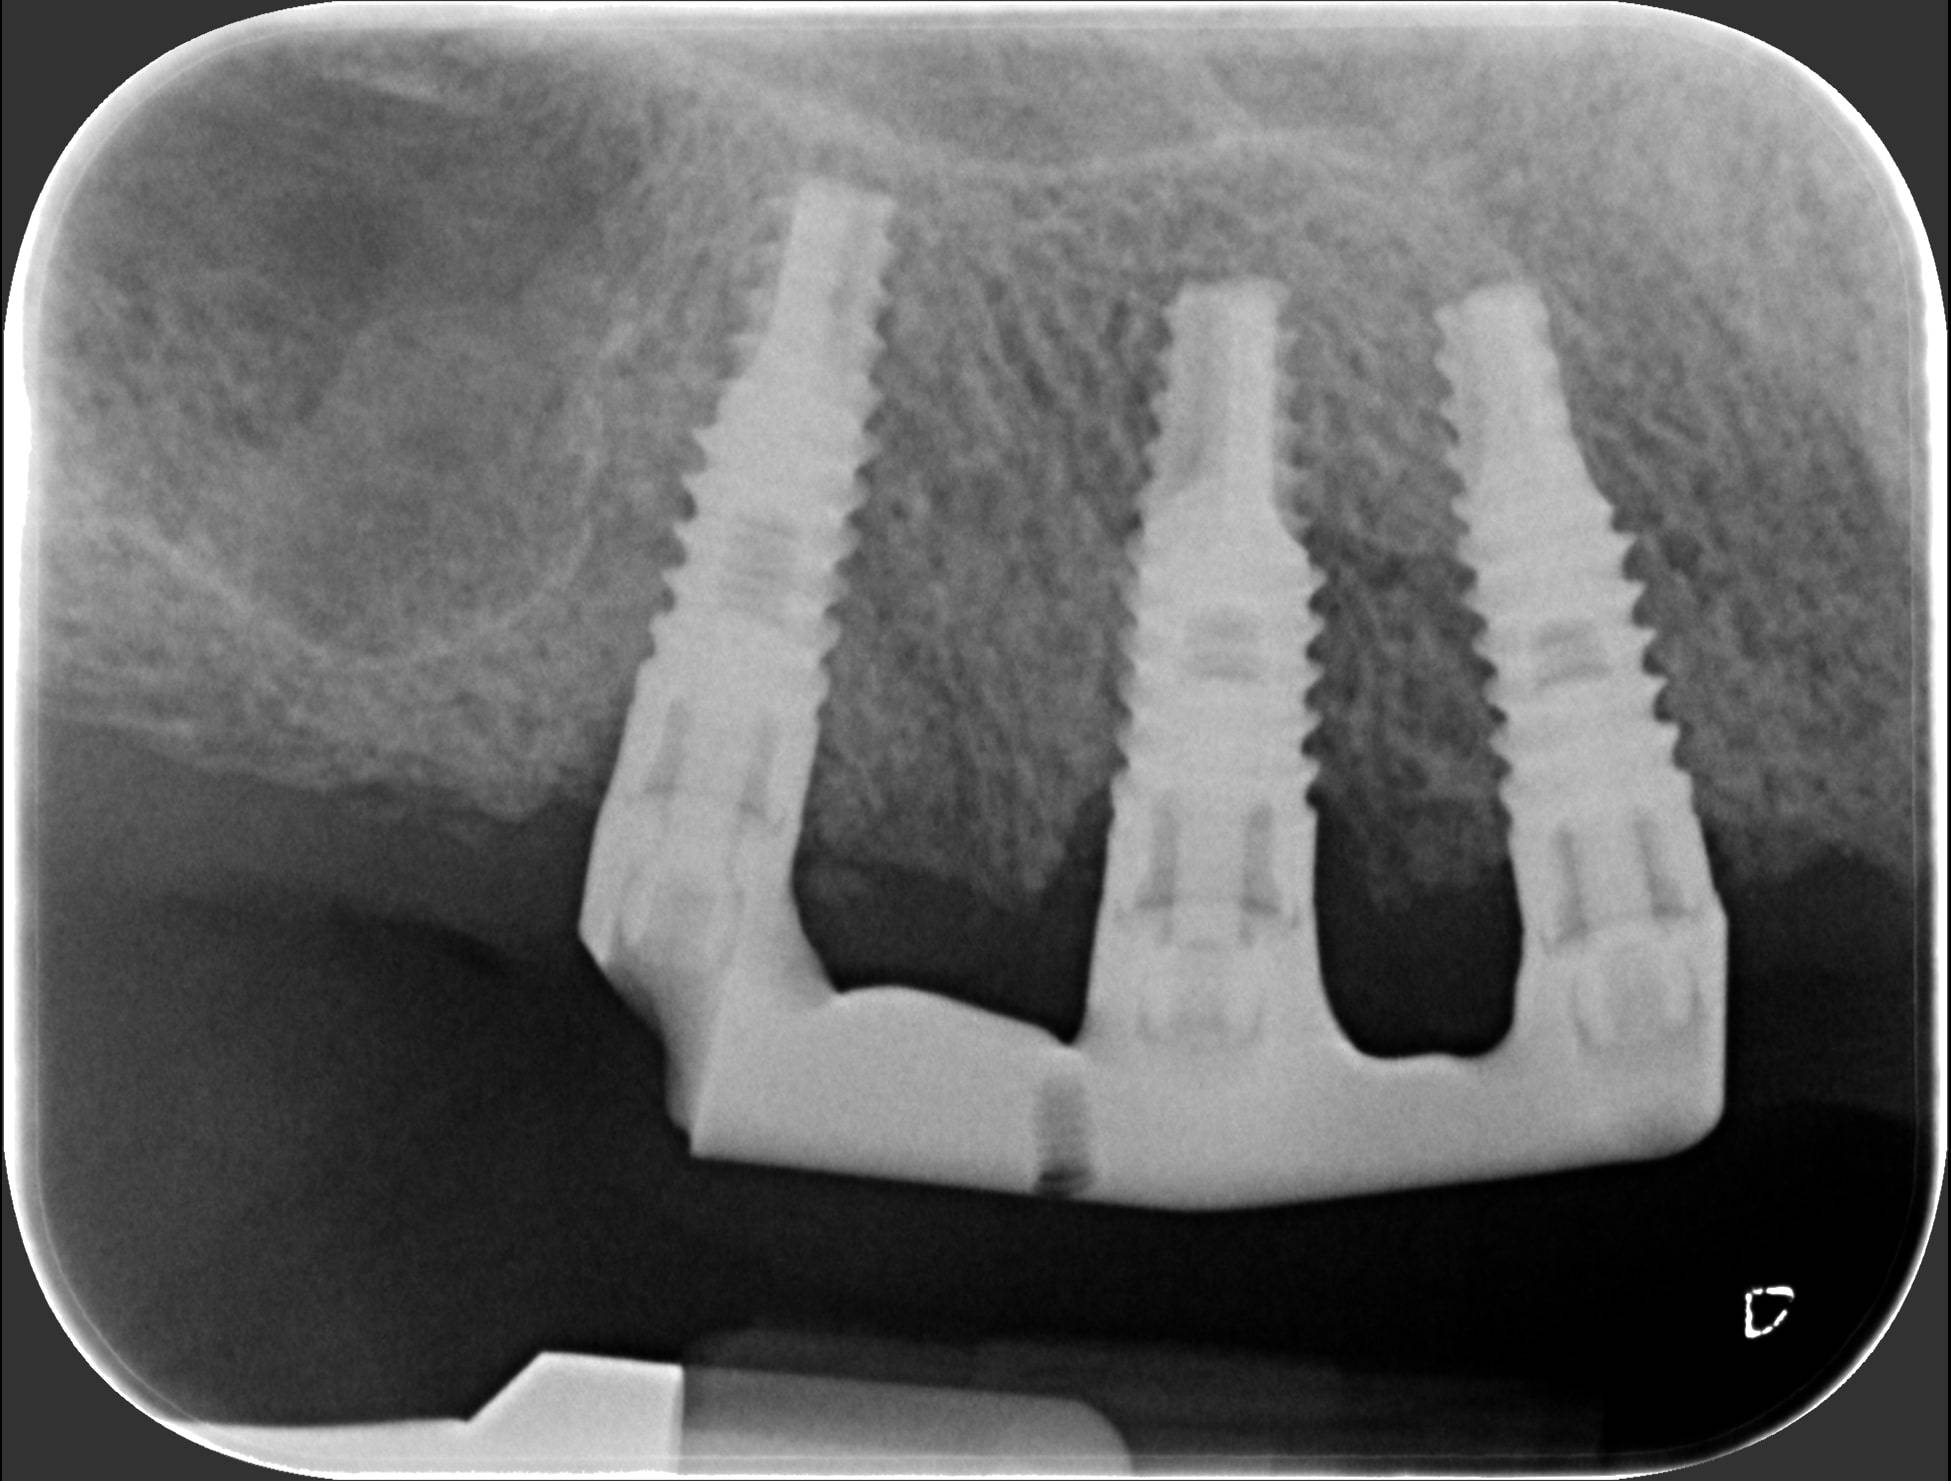

In questi casi la migliore soluzione, dopo aver estratto i quattro denti traballanti, è programmare un numero di impianti sufficiente ad eseguire una protesi fissa. Poi, una volta avvenuta l’osteointegrazione, si prende l’impronta di precisione; un laboratorio specializzato crea successivamente delle strutture metalliche in titanio (quelle che noi dentisti chiamiamo “primarie”), che poi vengono avvitate sugli impianti solidarizzandoli tra loro.

Puoi vedere le radiografie delle due barre avvitate nelle successive due foto. Sopra queste barre viene quindi avvitata l’ampia struttura metallica (che chiamiamo “secondaria”), che porta i denti artificiali di tutta l’arcata. E così, la signora si è ritrovata tutti denti fissi con cui può ridere, masticare e tornare ad una vita finalmente normale. Adesso confronta l’ultima foto con la prima e capirai come l’implantologia può cambiarti la vita in meglio. Questo è ciò a cui miriamo ogni giorno nello Studio dentistico del dott. Fabio Ballestrasse a Besana Brianza e se sei di Barzanò adesso sai a chi rivolgerti.